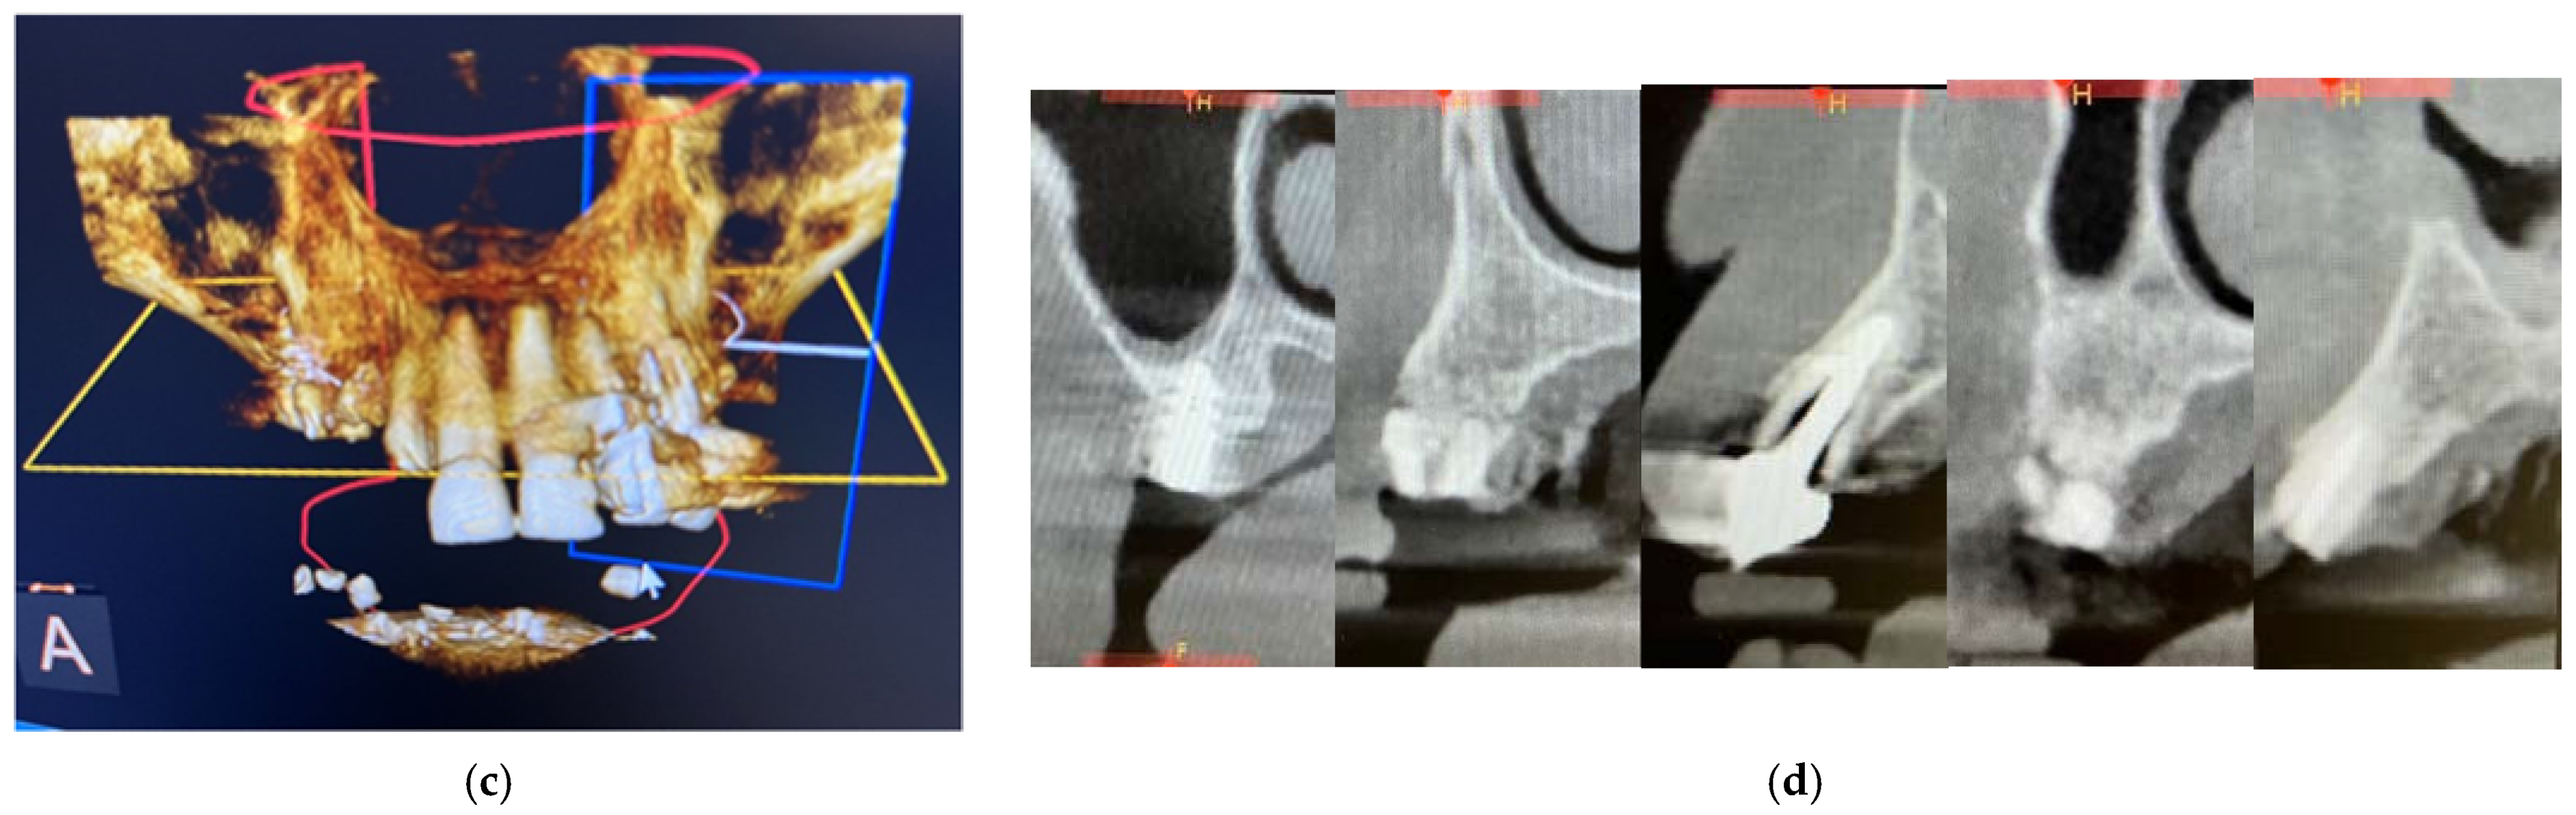

Surgical Procedure